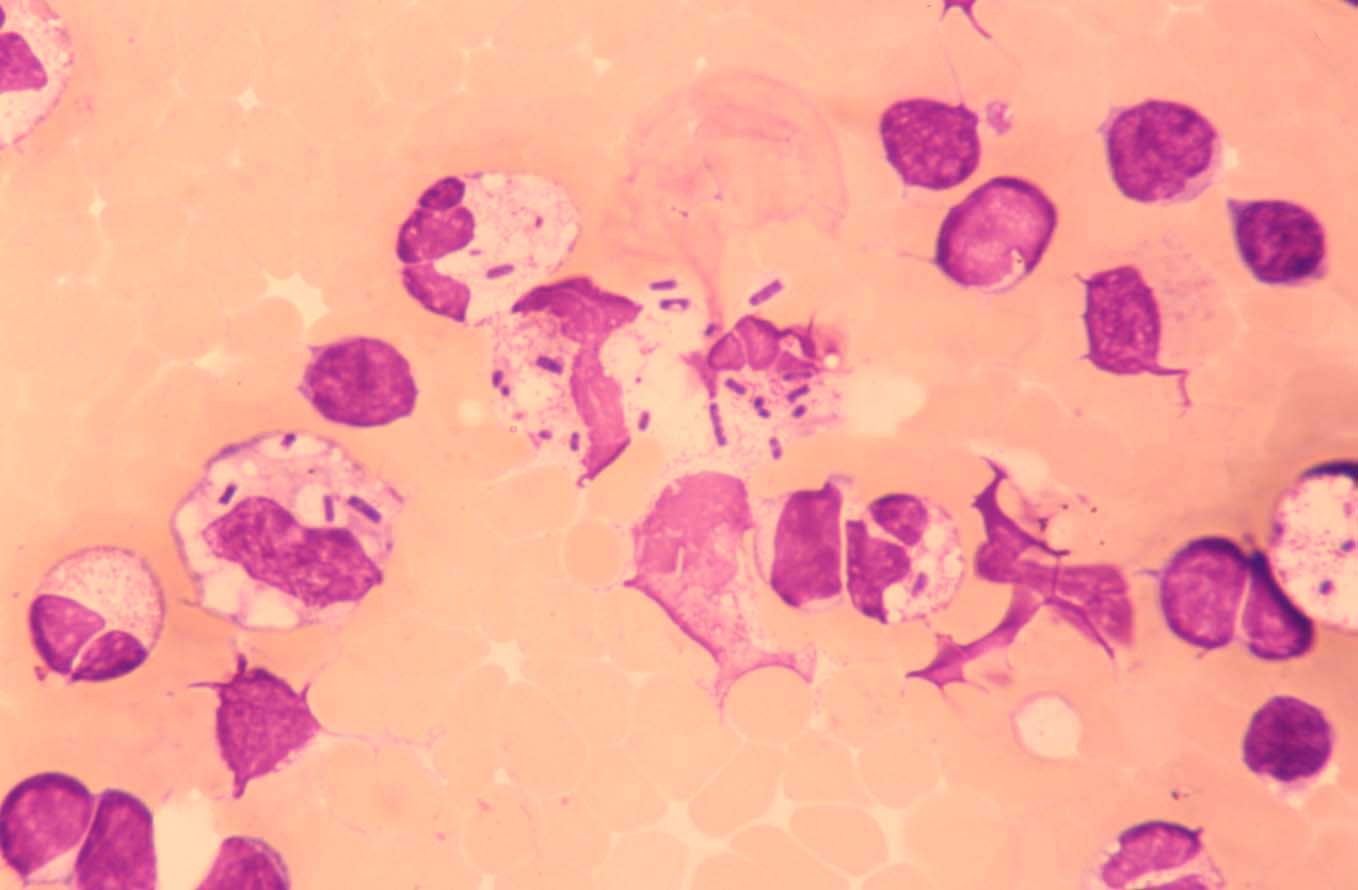

Phagozytierte Sporen und Pseudohyphen

Erstelldatum: 12.12.2004

Art: Zytologie

Material: Pleuraerguss

Färbung: panoptisch

Makrophagen mit phagozytierten Pilzsporen und kleinen Pseudohyphen.

(Mikroskopische Objektivvergrößerung X100)